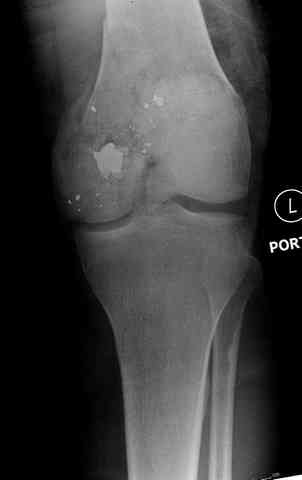

Здесь представлены несколько случаев лечения огнестрельного перелома

2 внутрисуставной перелом дистального бедра с удалением пули